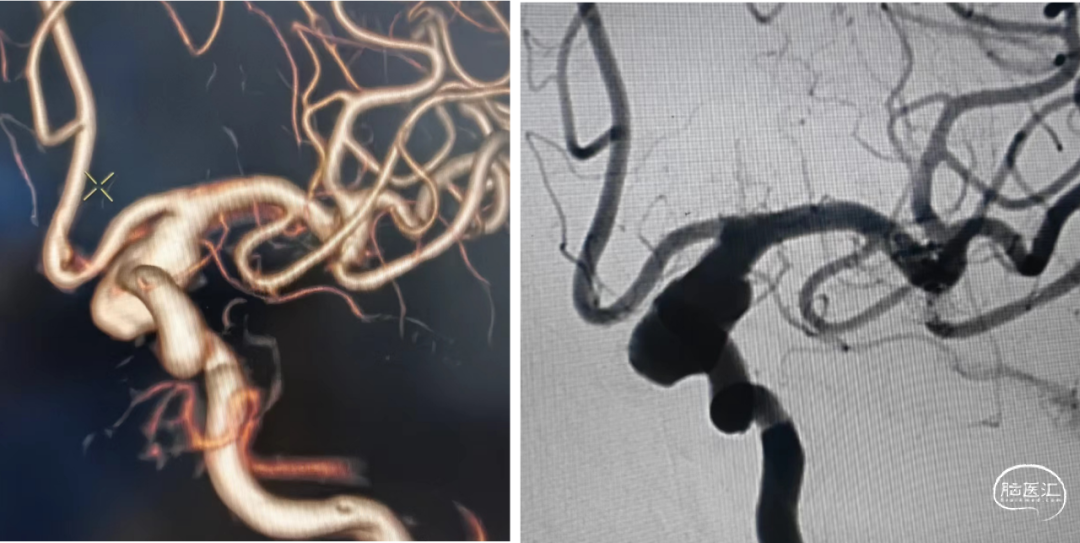

CTA影像检查:

左侧颈内动脉造影:

右侧颈内动脉造影:

左侧颈内动脉末端夹层动脉瘤、左侧大脑中动脉分叉部动脉瘤、右侧颈内动脉脉络膜前动脉处动脉瘤。

a.左侧颈内动脉末端夹层动脉瘤形状不规则且囊体较大,大脑中分叉部动脉瘤有一分支发出,这两处动脉瘤相对危险性高,此次优先处理;右侧脉前动脉瘤二期治疗。

b.左侧颈内动脉末端夹层动脉瘤呈不规则长条形改变,脉络膜前动脉在瘤体远端发出,若选用传统的弹簧圈栓塞治疗,则有可能出现分支闭塞,引起并发症,因此考虑使用血流导向装置密网支架覆盖载瘤动脉,避免出现分支血管闭塞。